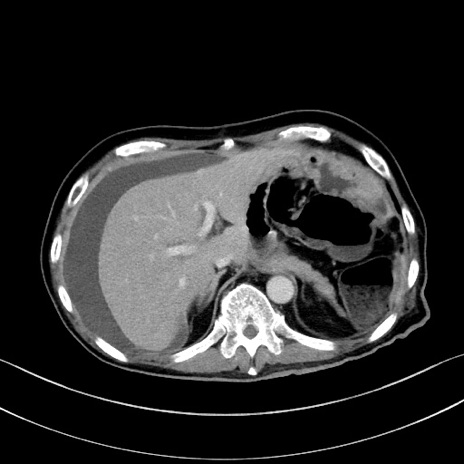

症例28(横断像)

【症例】60歳代男性

【主訴】嘔吐

【現病歴】胃癌にて胃全摘後。食思不振が悪化し、夜中に嘔吐することがある。

【既往歴】胃癌、胃全摘、脾摘、胆摘後

【データ】WBC 5900、CRP 10.56